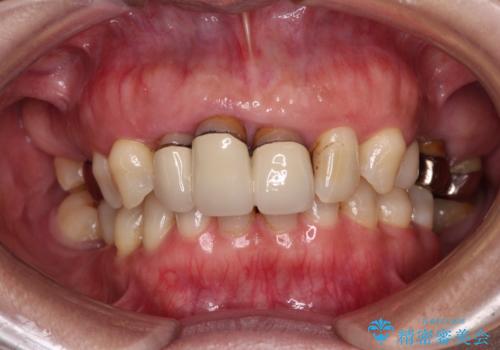

- 20年以上前に装着した前歯のメタルセラミックが不自然であることを気にして来院された患者様です。

歯肉の位置が変わり、変色した歯根が露出しているため、金属の土台をファイバーコアに交換した上で、オールセラミッククラウンにて補綴することとしました。